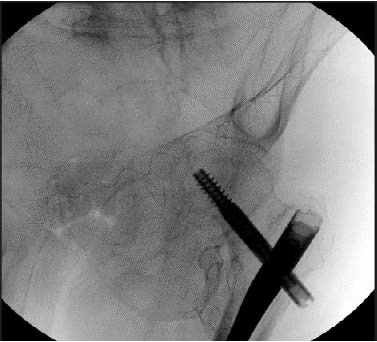

A 66-year-old male sustained a left acetabular fracture after a fall. The patient’s past medical history was significant for a previous left hip fracture and left-sided weakness from 2 left sided strokes requiring the use of a hemiwalker. CT scan revealed a typical geriatric both-column acetabular fracture with mild protrusio. The patient failed two days of conservative treatment, complaining of significant pain and discomfort and surgical intervention was requested. The patient was treated operatively through a novel approach to the posterior column traversing down the gluteus medius pillar and curving posteriorly to the acetabulum to go down the posterior column. This novel corridor is possible only with the use of a flexible implant.The anterior column was treated in a standard retrograde fashion, though a much longer construct was made possible by using a flexible implant. The IlluminOss implants were inserted, filled with liquid monomer, and cured using visible light. On postoperative day 1, the patient was weight-bearing as tolerated using a hemiwalker and released from the hospital the following day.At 2-weeks post op, patient was weight-bearing as tolerated with no displacement noted on radiographic imaging.